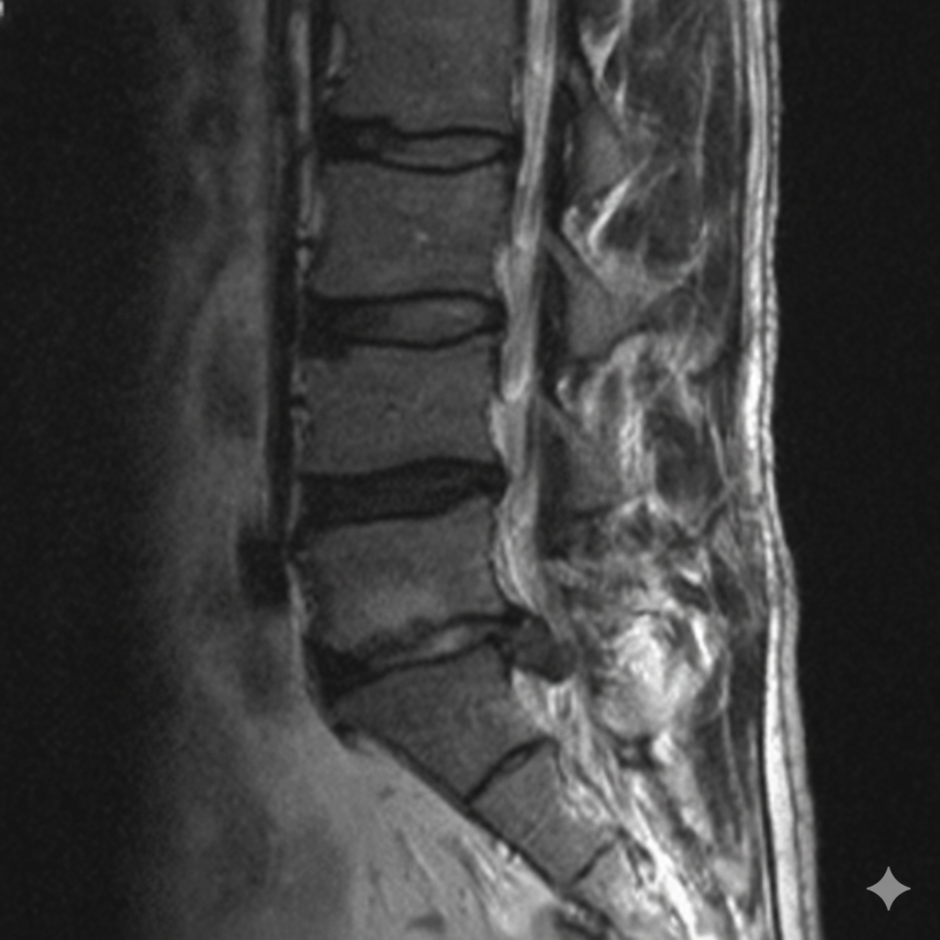

坐骨神経痛の原因が

「腰椎椎間板ヘルニア」や

「腰部脊柱管狭窄症」と

病院で診断されることは多いのですが,

では,椎間板ヘルニアや脊柱管狭窄症は

整体で治るでしょうか?